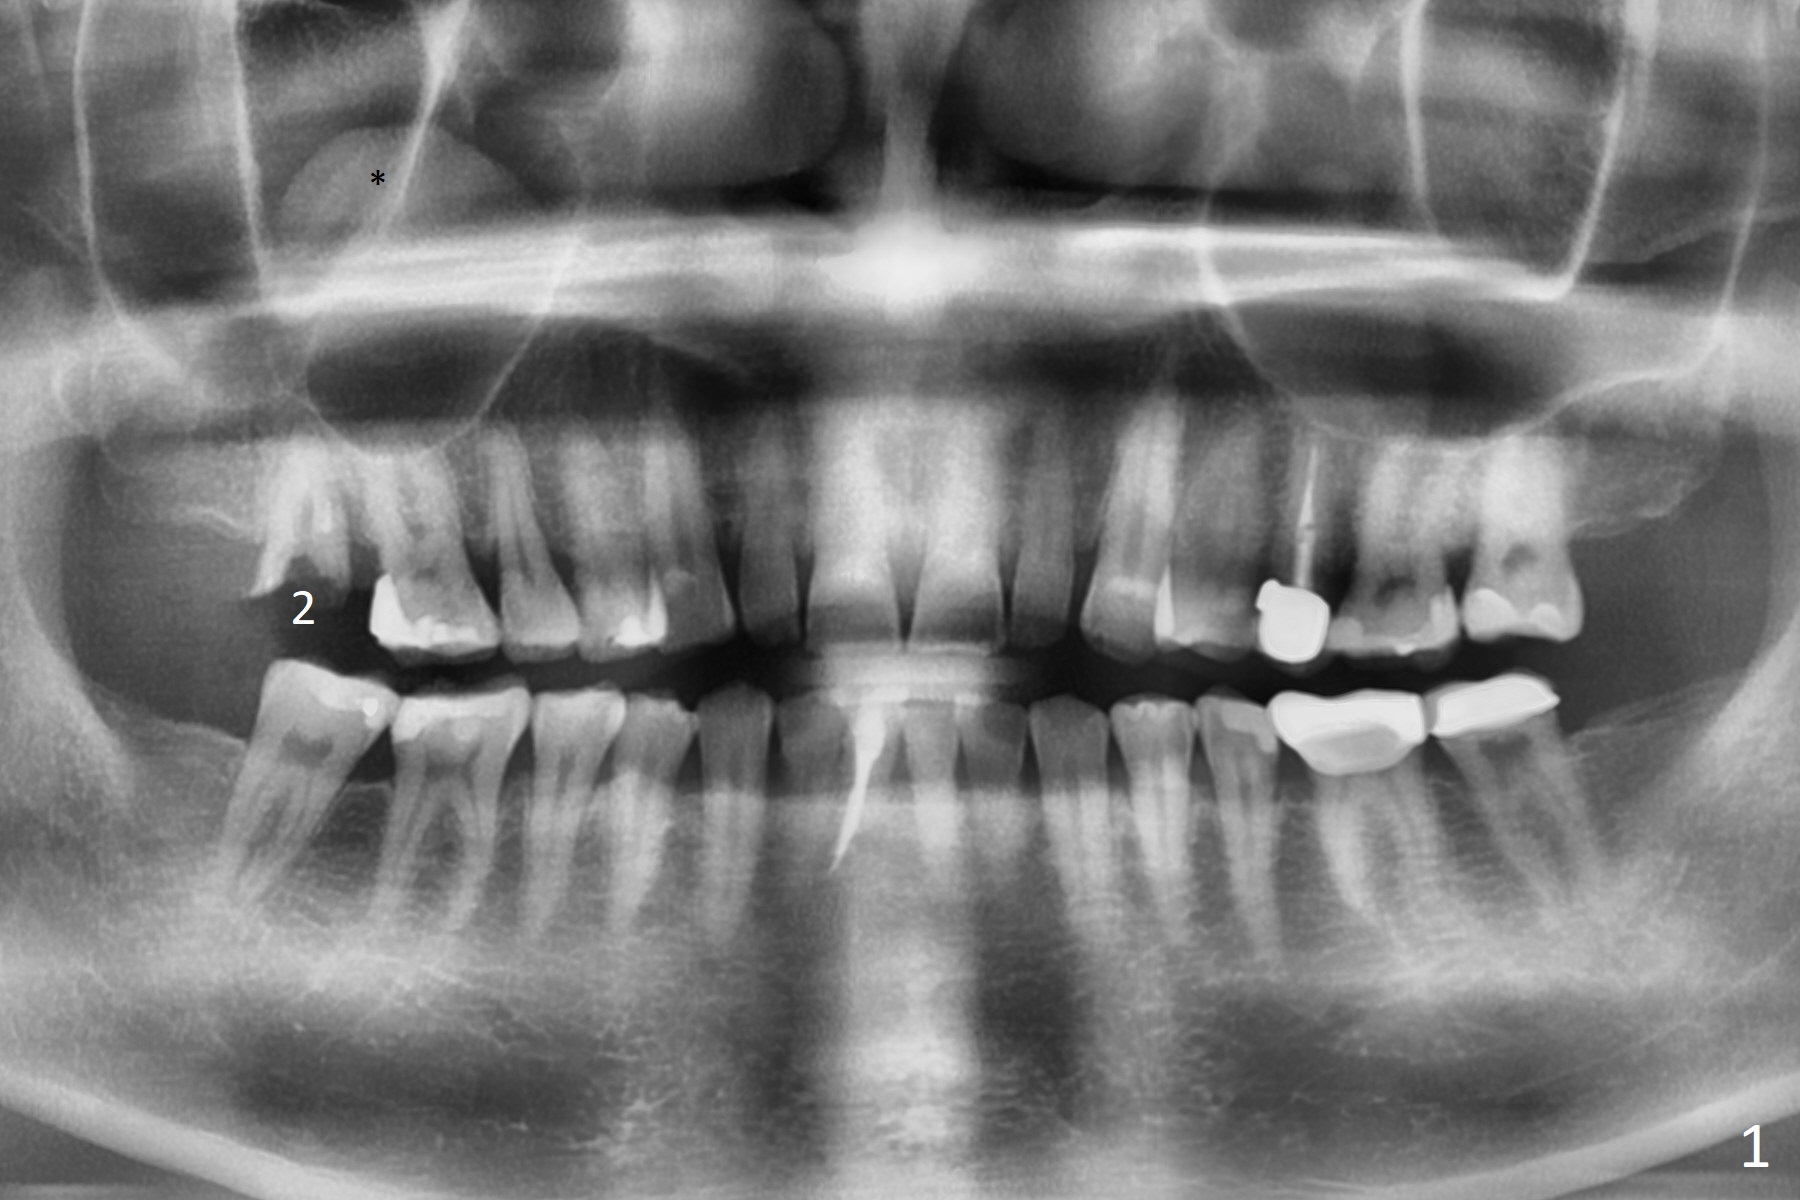

A 51-year-old man agrees to have #2 residual root to be extracted for implant. Panoramic X-ray (Fig.1) and CT coronal section (Fig.2) show maxillary sinus mucocele (*). A 5x10 mm implant will be placed not to intrude into the sinus (Fig.2,3). In case sinus membrane perforation, prepare PRF membranes for repair. The apex of the implant will be engaged to an apparent sinus septum for stability (Fig.4,5,7 arrowheads). Fig.4,5,6 are sagittal and coronal sections and 3-D image of Fig.3 without an implant at #2, while Fig.7 is the inferior view of Fig.6 (arrow).